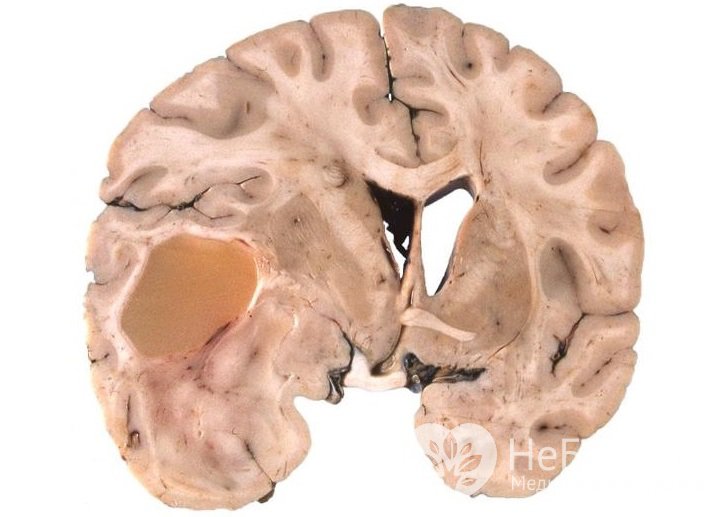

Астроцитома – первичная опухоль головного мозга, исходящая из астроцитов (звездчатых клеток) нейроглии. Астроцитомы различаются по клиническому течению, степени злокачественности, локализации. Заболеваемость составляет от 5 до 7 случаев на 100 000 населения.

У взрослых астроцитомы обычно локализуются в белом веществе больших полушарий головного мозга. У детей они чаще поражают ствол мозга, мозжечок или зрительный нерв.

Астроцитома – глиальная опухоль головного мозга, возникающая из астроцитовТочные причины, приводящие к развитию астроцитом, на сегодняшний день неизвестны. Предрасполагающими факторами могут быть: